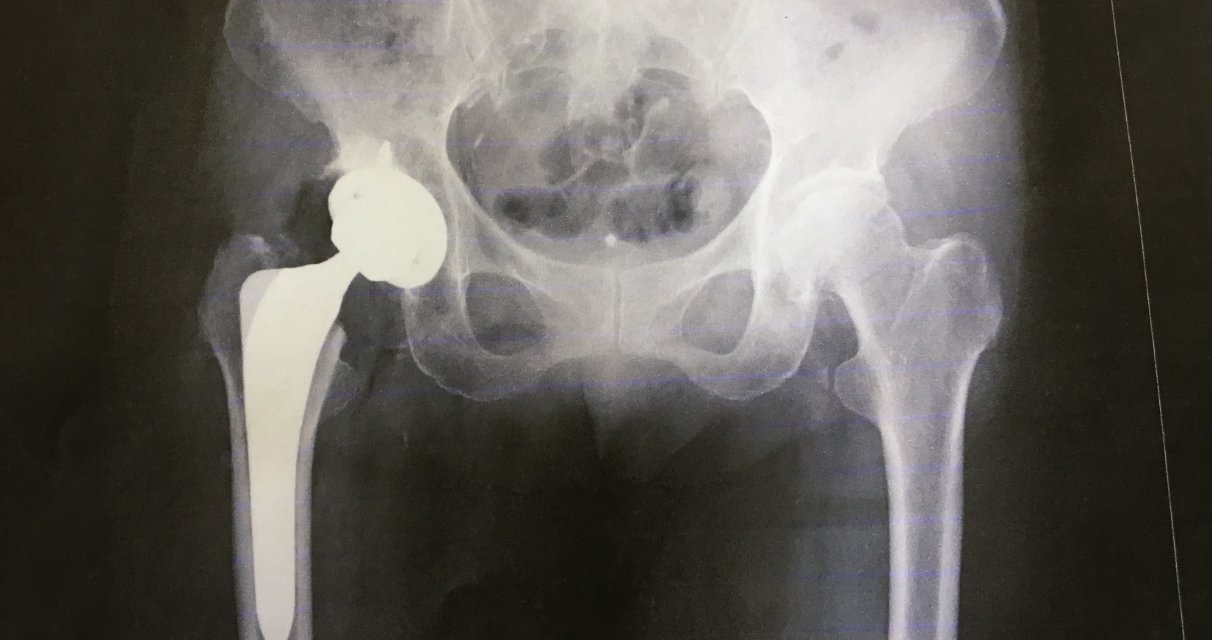

股関節

変形性股関節症/特発性大腿骨頭壊死症/大腿骨頸部骨折/

単純性股関節炎/臼蓋形成不全(先天性股関節脱臼)/

関節リウマチ/化膿性股関節炎

股関節痛の治療は薬物療法やリハビリテーション、安静といった保存療法から手術まで幅広い治療が必要になります。適切に原因、病態を把握し、早期に治療・予防を開始し、将来的な手術のリスクの回避を目指します。また、手術の必要な場合は適切な時期に手術を受けられるよう定期的な検査、関連病院への紹介を致します。